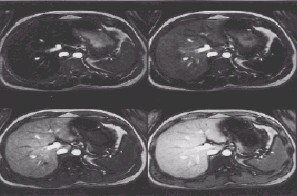

Figure 2. Abdomen with IR Prepared